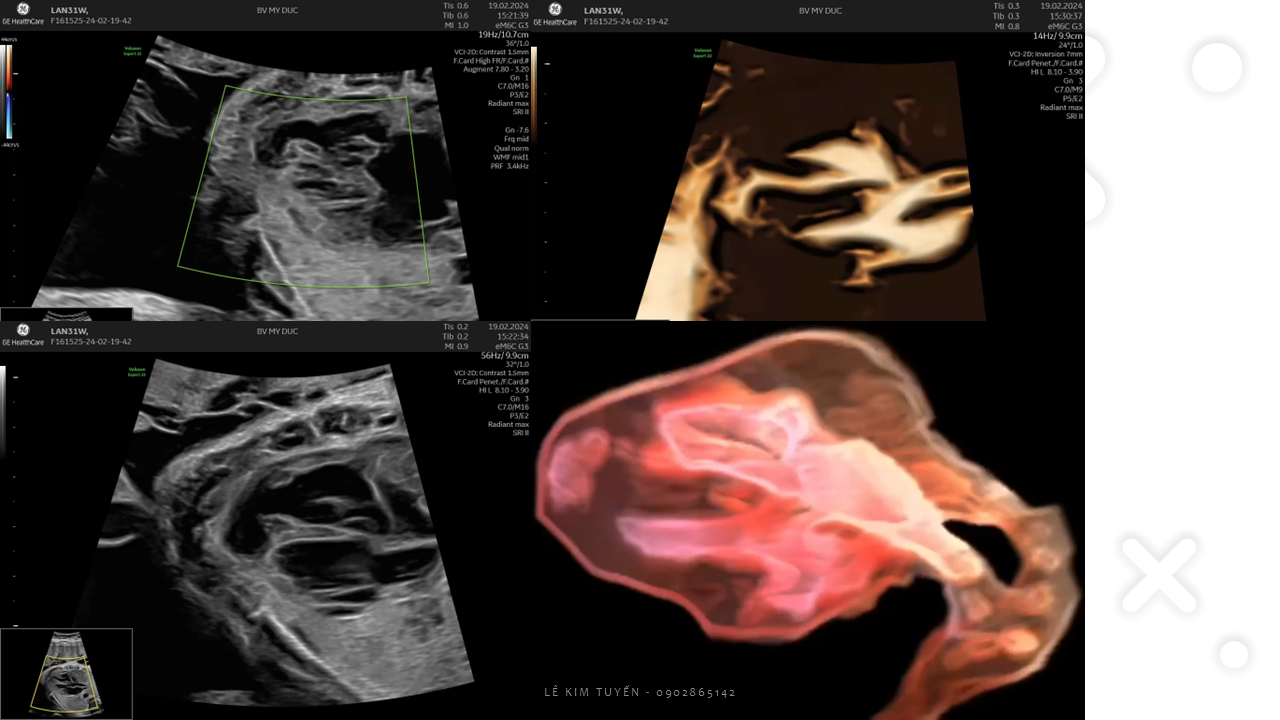

Siêu âm tim thai - Các kỹ thuật hiện đại

TS. BS. Lê Kim Tuyến

Bệnh viện Tim Tâm Đức